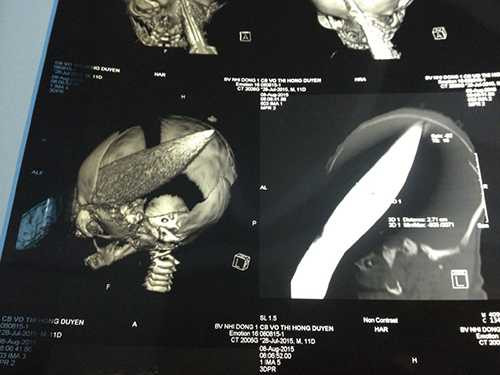

![]() |

| Các bác sĩ của BV Nhi Đồng 1 đã tiến hành ca mổ 3 tiếng, lấy con dao ngập sâu vào hộp so 11cm ra khỏi đầu cháu bé sơ sinh 12 ngày tuổi. (Ảnh: T.Huyền) |

Trong một diễn biến khác, tại BV Nhi đồng 1 TP.HCM, ê kíp khoa Hồi sức Sơ sinh đã trắng đêm theo dõi diễn biến sức khoẻ cháu bé sau ca phẫu thuật rút dao từ hộp sọ.

Trưa 9/8, trao đổi với PV, BS.Nguyễn Thanh Hùng, Giám đốc Bệnh viện cho biết, sau một đêm theo dõi, dấu hiệu sinh tồn của bé sơ sinh tạm thời ổn định.

Theo bác sĩ Đào Trung Hiếu, Phó GĐ (trưởng ê kíp mổ cứu cháu bé ngày 8/8), tới nay bé sơ sinh không bị sốt.